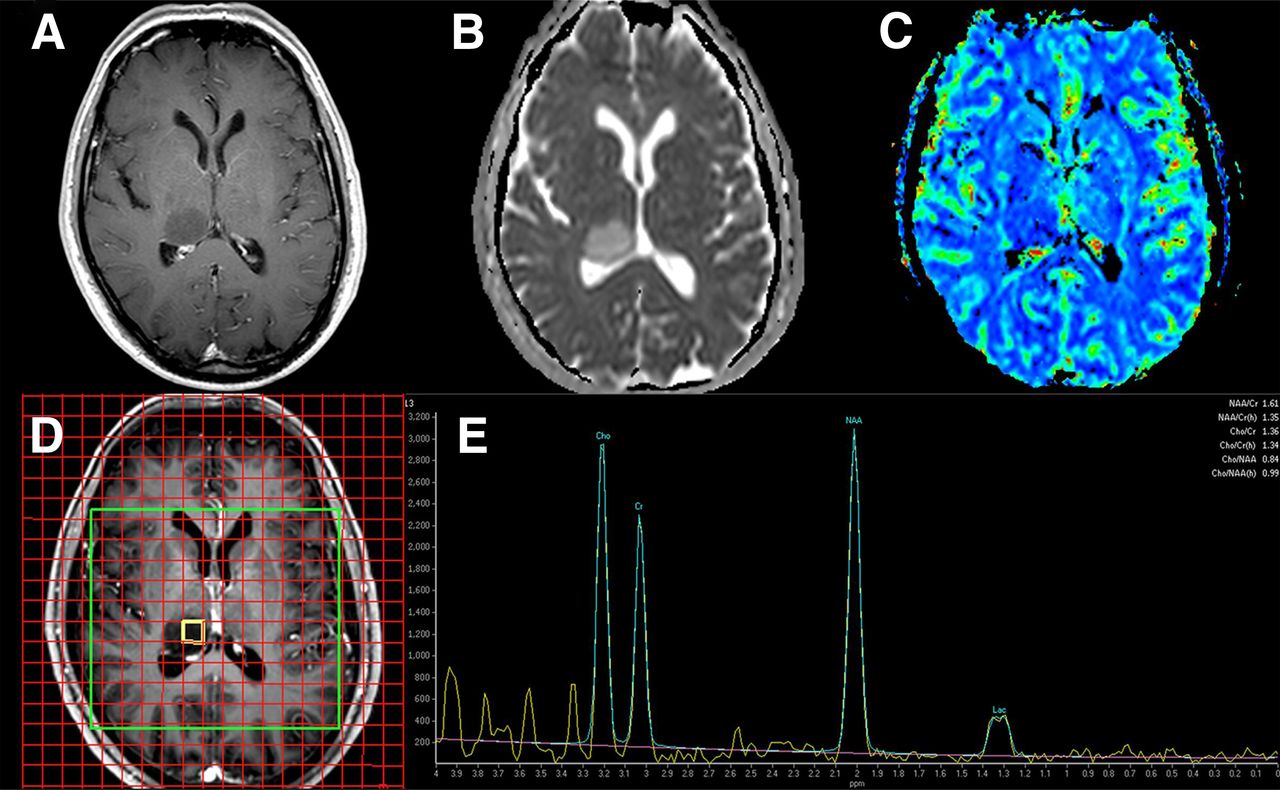

تصویربرداری MRS

تصویربرداری MRS تصویربرداری MRS یک آزمایش تشخیصی غیرتهاجمی برای اندازه گیری تغییرات بیوشیمیایی مغز ، به ویژه وجود تومورها است. در حالی که تصویربرداری تشدید مغناطیسی (MRI) محل تشریحی تومور را مشخص می کند ، تصویربرداری MRS ترکیب شیمیایی بافت طبیعی مغز را با بافت تومور غیرطبیعی مقایسه می کند. این آزمایش همچنین می تواند برای تشخیص تغییرات بافتی در سکته مغزی و صرع استفاده شود. تصویربرداری MRS در همان دستگاه MRI معمولی انجام می شود. در اسکن MRI از

آنالیز MRS

آنالیز MRS در آنالیز MRS توالی پالس در استفاده برای آنالیز داده ها و ثبت داده ها مهم است. در حالت ایده آل ، از الگوریتم های کاملاً خودکار منحنی-اسپتکتروسکوپی برای ایجاد برآورد کمی از هر غلظت متابولیت باید استفاده شود. با این حال ، اگرچه چنین نرم افزاری وجود دارد و غالباً در مطالعات تحقیقات بالینی مورد استفاده قرار می گیرد ، اما در عمل بالینی معمول ، جایی که تفسیر بصری معمول است ، از آن کم